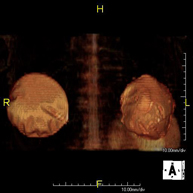

- Kidney MRI

This non-invasive diagnostic procedure uses an electromagnetic field and radio waves (from a transmitter and receiver) to acquire high-definition anatomical images of the kidneys. It is a radiation-free procedure. It is performed to study any localised injury in both kidneys. Paramagnetic contrast (gadolinium) is usually required to characterise the lesions.